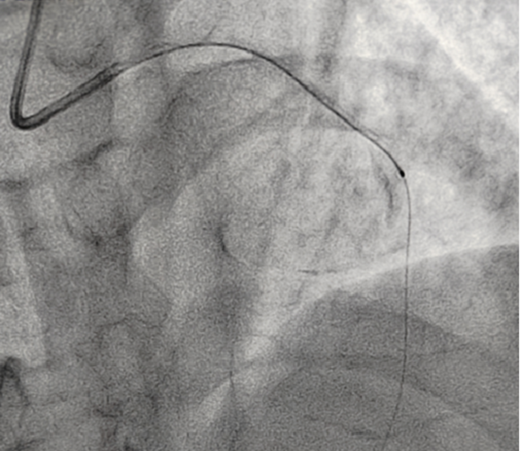

立即啟動綠色通道,急診冠脈造影,結(jié)果顯示前降支近段閉塞,血栓負(fù)荷較重,先后給予血栓抽吸及球囊擴(kuò)張,血流恢復(fù)正常。李桂武主任和劉興剛主任發(fā)現(xiàn)患者近段狹窄達(dá)70%,且中遠(yuǎn)段嚴(yán)重狹窄伴鈣化,此時不適合同期植入支架,如植入支架可能會引發(fā)血管破裂危及生命。當(dāng)務(wù)之急是快速評估出患者是否可以下手術(shù)臺,選擇擇期進(jìn)行處理,但僅根據(jù)造影結(jié)果又很難做出判斷,李桂武主任和劉興剛主任快速討論研究最后一致決定,給予患者行冠脈OCT檢查,明確病變性質(zhì)。

經(jīng)OCT檢查結(jié)果顯示:前降支中段鈣化,內(nèi)膜光滑,最小管腔面積僅為1.19 mm2。近段斑塊破裂,可見血栓影,最小面積為2.63mm2??蛇x擇先進(jìn)行抗栓治療,擇期處理冠脈病變。這讓張先生懸著的一顆心終于放下來。

OCT檢測是將一條頭端帶光學(xué)透鏡的成像導(dǎo)管放在冠脈血管里,通過高速旋轉(zhuǎn)回撤,不到3秒鐘就可以幫我們診斷清楚血管里面的結(jié)構(gòu)和斑塊性質(zhì),就像直接把眼睛放進(jìn)血管里看一樣,整個診斷過程非常安全可靠。